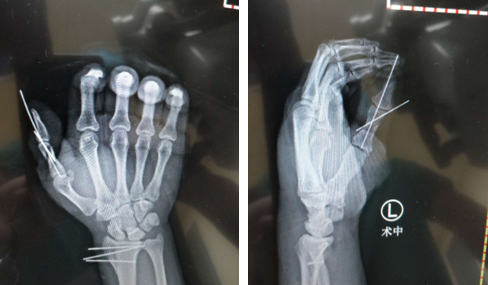

患者被推进手术室时,差不多已经是他伤后6小时了。术中,唐洪伟医生手术团队用患者示指桡侧的指固有动脉转位修复其拇指血管,重建血运,拇指尺侧神经和示指桡侧神经吻合,拇指桡侧神经与背侧桡神经浅支吻合。再用患者环指浅腱重建其拇指屈指功能,用示指固有伸肌重建其伸拇功能。手术非常顺利,一期完成了患者的左手拇指血管、神经和肌腱的重建,避免了二次手术。不但为患者减轻了痛苦,而且减少了治疗费用。